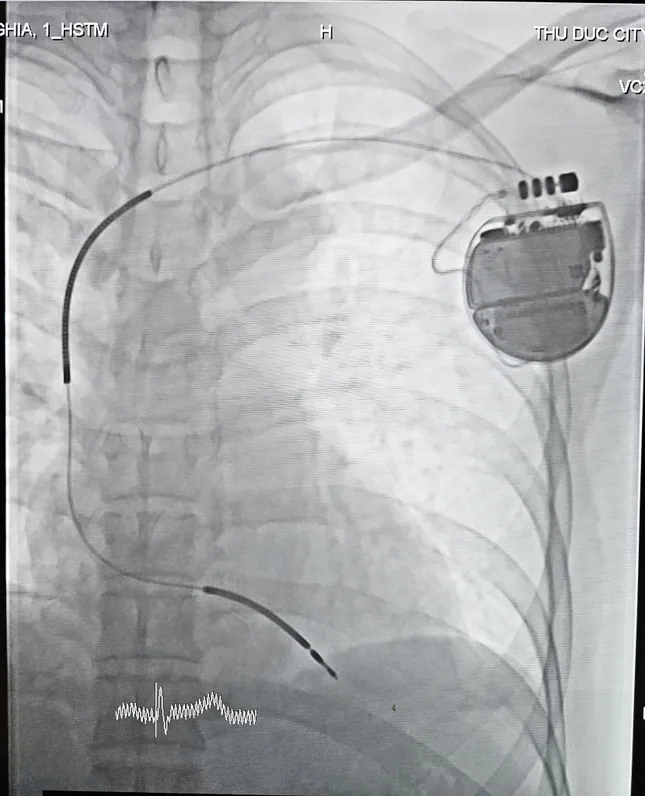

Các bác sĩ tiến hành cấy máy phá rung tự động, ngăn chặn nguy cơ đột tử cho bệnh nhân

Ở lần đột tử thứ nhất, các bác sĩ đã chỉ định cho bệnh nhân cấy máy phá rung tự động ( ICD ) để ngăn ngừa nguy cơ đột tử do rối loạn nhịp thất. Tuy nhiên, do điều kiện kinh tế khó khăn nên thời điểm đột tử lần thứ nhất bệnh nhân chưa cấy máy dẫn đến tiếp tục bị ngưng tim khi ngủ lần thứ hai.

Thiết bị được đặt dưới da có khả năng kiểm soát nguy cơ rối loạn nhịp thất cho bệnh nhân

Sau khi được cứu sống lần thứ hai, các bác sĩ đã tiến hành cấy ICD cho anh N. Ca phẫu thuật kéo dài 60 phút diễn ra thuận lợi: thiết bị được đặt dưới da vùng ngực, các điện cực nối trực tiếp vào buồng tim để giám sát và xử lý tình trạng rối loạn nhịp nguy hiểm. Sau đặt máy thành công, sức khỏe người bệnh đã ổn định, không ghi nhận nhịp nhanh thất hoặc rung thất tái phát.